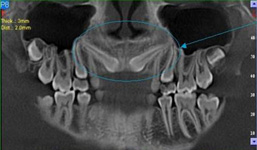

Je speciální zubní digitální tříprostorový tomograf (3D), který umožňuje na základě jediného snímkování vytvořit všechny typy RTG zobrazení, které jsou pro lékaře potřebné. Díky používané technologii tzv. „kuželového paprsku“ a speciálním senzorům je výrazně zmenšená dávka záření - o více jak 80% proti klasickému CT vyšetření. To je významné zejména u dětí. Pomocí tohoto přístroje je možné zjisti skutečnou situaci v čelistních kostech pacienta tedy množství kosti - můžeme změřit skutečnou šířku i výšku kosti, i kvalitu kosti (hustotu) v místě uvažované implantace. 3D (tříprostorové) zobrazení umožňuje zvýšit prostorovou představu operatéra ještě před vlastní operací a zároveň pacientovi lépe objasnit a ukázat oblast plánovaného zavedení implantátu.

Pacient „neumí číst“ RTG snímky, ale díky 3D zobrazení vidí „svoji skutečnou čelist“ - např. jak je nízká či úzká, vidí průběh nervu nebo velikost čelistní dutiny, což mu umožní i pochopení nutnosti v některých případech provést pomocné zákroky ještě před vlastním zavedením implantátu (viz. kostní štěp, sinus lift, kostní granulát...).

Vyšetření pomocí tohoto přístroje používáme i ve stomatochirurgii (zlomeniny čelistí, zuby moudrosti, cysty, onemocnění čelistního kloubu), ortodoncii (retinované zuby, nadpočetné zuby), parodontologii atd.

NewTom Giano

Jedná se o nejnovějším přístroj ze skupiny dentálních hybridních CBCT (3D) + 2D (pan i ceph) systémů. Opět umožňuje na základě jediného snímkování vytvořit všechny typy RTG zobrazení, které jsou pro lékaře potřebné. Používaná technologii tzv. „kuželového paprsku“ a speciální senzory pro minimální zátěž při snímkování pacienta.

Vyšetření pomocí tohoto přístroje (nebo 3D DVT - NewTom) a získaná data používáme pro každou implantaci, dále ve stomatochirurgii (zlomeniny čelistí, zuby moudrosti, cysty, onemocnění čelistního kloubu), ortodoncii (retinované zuby, nadpočetné zuby), parodontologii atd.